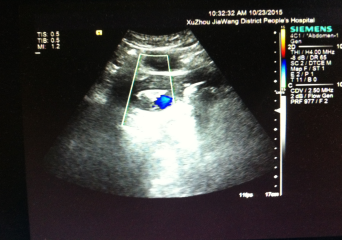

2015-10-23彩超:子宫大小约5.7cmx4.1cmx3.6cm,肌层回声欠均匀,宫体右后壁肌层内探及范围约100pxx2.6cmx1.3cm不均质高回声,界尚清,周边及内部未示明显血流。左侧卵巢大小约2.6cmx2.2cm,右侧卵巢大小约3.2cmx2.7cm。盆腔未见明显积液声像。诊断意见:宫体右后壁不均质高回声:胎盘残留并机化?